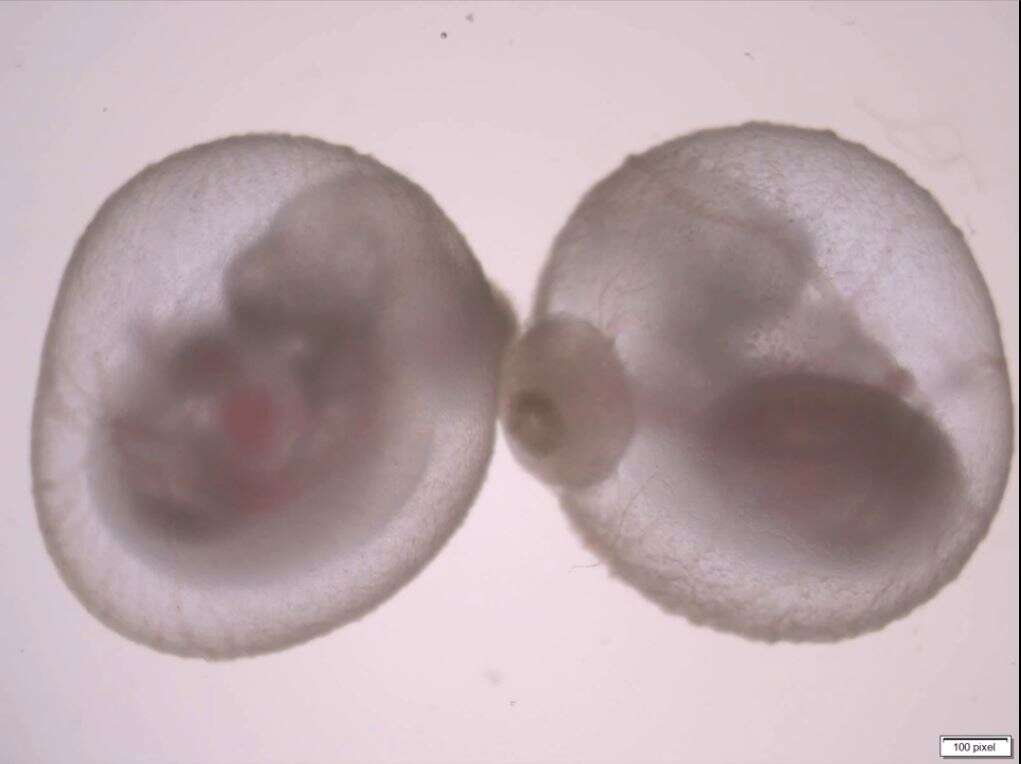

במשך שבע שנים, באמצעות ניסוי וטעייה, כיוונון עדין ובדיקות חוזרות ונשנות, פיתחו במעבדתו של פרופ' חנא, המתמחה בתאי גזע עובריים, שיטה דו-שלבית המאפשרת לגדל עוברי עכברים תקינים מחוץ לרחם כבר משלבי ההיריון הראשוניים – מהשלב שבו העוברים הם לא יותר מאשר גוש אחיד של תאים זהים ועד לשלב שבו הם בעלי גוף מוגדר היטב ואיברים פנימיים.

בשלב הראשון גידל צוות המחקר בהובלת אלחנדרו אגילרה, ד"ר ברנרדו אולדק, ד"ר ראדה מסארווה המנוחה, ד"ר נועה נוברשטרן וד"ר איתי מזאה, לשעבר תלמיד מחקר במעבדתו של פרופ' חנא וכיום חוקר במרכז הרפואי רמב"ם, עוברים בני כמה ימים – בשלב ההתפתחותי שבו הם מעין כדורים המורכבים מ-250 תאי גזע זהים.

המדענים הצליחו לגרום לכדורים אלה להשתרש במצע גידול מיוחד בתוך כלי מעבדה – בדומה לאופן שבו הם משתרשים בדופן הרחם. בכך הם הצליחו לחקות את השלב הראשון של ההתפתחות העוברית, שבמהלכו מכפיל העובר את גודלו פי כמה וכמה, בעודו מתמיין לשלוש שכבות של תאים: פנימית, אמצעית וחיצונית.

לאחר כיומיים – עם כניסתם של העוברים לשלב הבא שבו מתפתחים האיברים השונים – הם הועברו לתמיסת הזנה בכוסות מעבדה זעירות שהוצבו על-גבי גלגלים. בהיעדר זרימת דם מהאם לשליה, תנועת הגלגלים אפשרה ערבוב מתמיד של חומרי ההזנה שבתמיסה המקיפה את העוברים. בנוסף דאגו החוקרים לנטר ולווסת את הכמות והלחץ של החמצן והפחמן הדו-חמצני בכלי המעבדה.